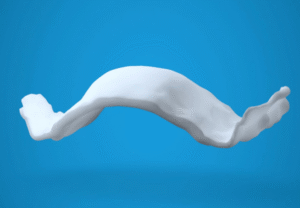

孩童上顎狹窄不可忽視,利用擴弓器引導牙弓生長

在兒童牙齒矯正臨床觀察中,「上顎(牙弓)狹窄」是一個經常被忽略、卻影響深遠的問題。許多家長帶孩子就診時,多數在意的是牙齒不整齊、暴牙或擁擠、也有家長認同黃汝萍醫

在兒童牙齒矯正臨床觀察中,「上顎(牙弓)狹窄」是一個經常被忽略、卻影響深遠的問題。許多家長帶孩子就診時,多數在意的是牙齒不整齊、暴牙或擁擠、也有家長認同黃汝萍醫